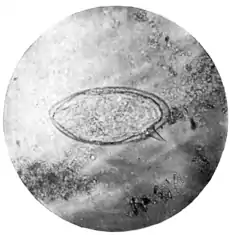

The occurrence of a schistosomum producing lateral-spined ova (Plate XIII. } Fig. 2) was noticed by Bilharzin 1851, but, believing the ova to represent peculiar capsules formed by the larvae after hatching, he confounded it with S. hœmatobium. After Bilharz several observers encountered female worms with lateral-spined ova in utero, and the idea of a dis- tinct species suggested itself to Sonsino and others, but this idea was at once discarded for other hypotheses. The lateral-spined ova being found only*[1] in the fæces of Egyptian patients suffering from hæmaturia, the majority of physicians held that the peculiar position of the spine was due to distortion of the eggshell in passing through the muscular coat of the rectum, forgetting that oviposition takes place in the submucous layer, and that lateral-spined ova are found in the uterus of the parent worm. Sonsino suggested that the two kinds of eggs might represent respectively male and female embryos. Looss surmised that the lateral-spined ova might be the product of unfertilized females; but if the lateral-spined are merely unfertilized ova as he suggests, it is difficult to explain the presence of the species in America, where the lateral-spined ova are the only ones found.

Fig. 2.—Lateral-spined egg of Schistosomum mansoni. (Microphotograph: Dr. Kerr.) |